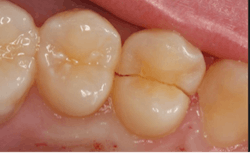

Cracked tooth

A cracked tooth is an incomplete fracture originating from the chewing surface of the tooth and extends vertically toward the root of the tooth. When the enamel is cracked it causes movement of the cracked area, causing the pulp area to become irritated. Eventually there becomes enough damage to the pulp to where the tooth can’t recover, which results in erratic pain. The pain can range from sensitivity with extreme temperatures and chewing to a constant, lingering pain that keeps one up at night. Excessive occlusal forces—the force exerted on opposing teeth when the jaws are closed or tightened—are the biggest factors to a cracked tooth. A cracked tooth is more centered on the chewing surface. Since a cracked tooth progresses toward the root, there is greater chance of root pathosis (disease to the root of the tooth).1,2

Treatment depends on the severity and depth of the crack. There are two kinds of cracks: treatable and untreatable (figure 3). For a treatable tooth, a crown is commonly the treatment option to restore the tooth and prevent progression of the crack. At this stage, early detection is crucial as the crack can steadily worsen, resulting in an extraction of the tooth (which would classify it as untreatable).